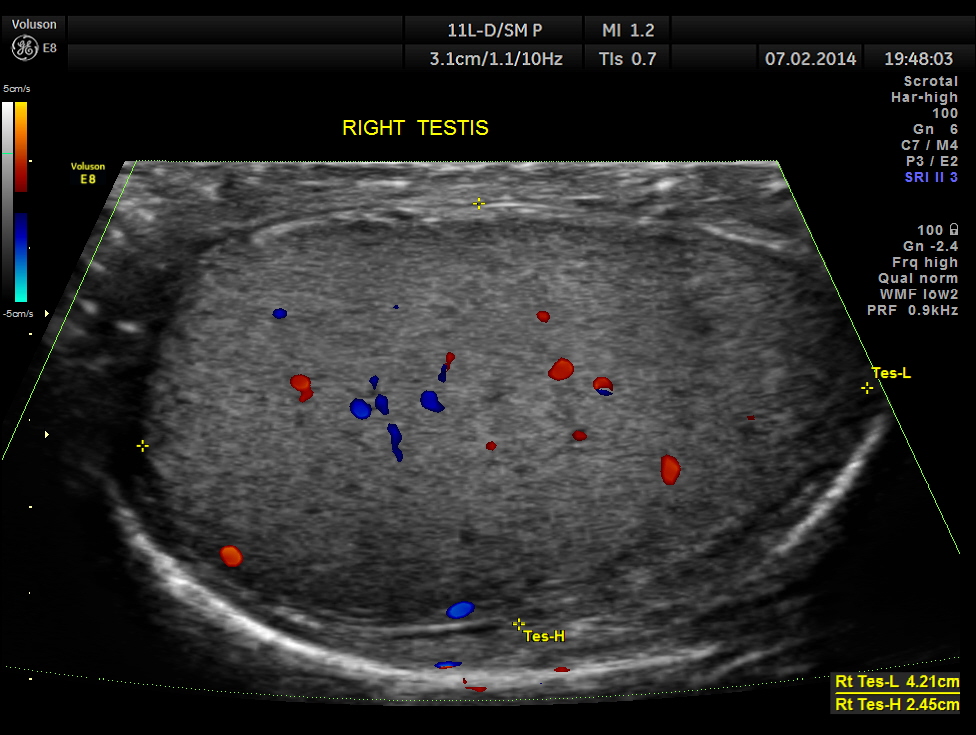

The following pictures show the testicles.Mild left hydrocele is also seen.

This patient had bilateral varicocele , left side being more prominent. Mild left hydrocele was also present.